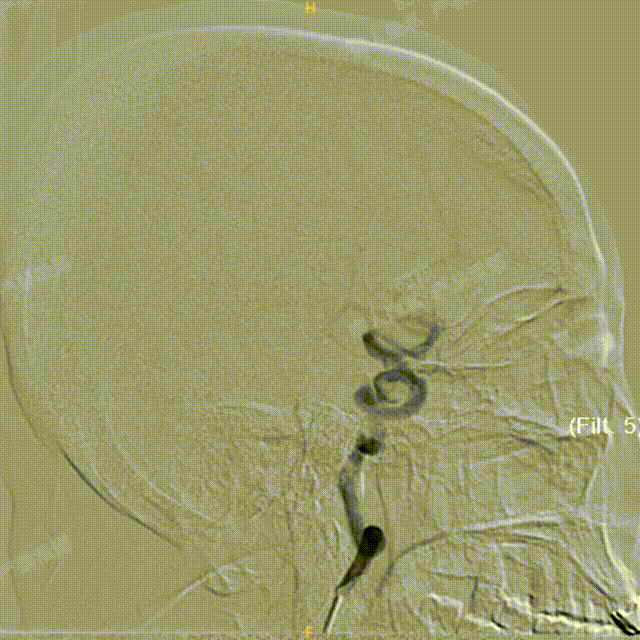

术中DSA造影:左侧颈内动脉正、侧位及3D造影,显示左侧颈内动脉后交通段动脉瘤。

术中DSA造影:右侧颈总动脉3D造影及右侧锁骨下正位造影。

Headway™ 27 156cm微导管内输送FRED 4518血流导向密网支架,系统远端精准定位于预计着陆区以远3-5mm,回撤微导管原位释放支架,头端锚定在颈内末端处。

正位

①输送导丝头端

②支架远端扩口显影点

③有效段起始点

④支架近端扩口显影点

确认支架远端定位于计划位置,预估近端可完全覆盖动脉瘤颈,且锚定距离充足。继续平衡释放系统,确保支架整体充分打开且贴壁良好后,解脱支架。

工作角度

①支架远端扩口显影点

②有效段螺旋显影丝

③支架近端扩口显影点

造影确认,载瘤动脉通畅、支架远端分支血流通畅、支架贴壁良好、动脉瘤内造影剂滞留。